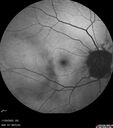

Traumatic Peripapillary Subretinal Hemorrhage1 views16 year old hit in eye with finger during basketball. Vision is 20/25 and there is a peripapillary hemorrhage.Apr 13, 2026